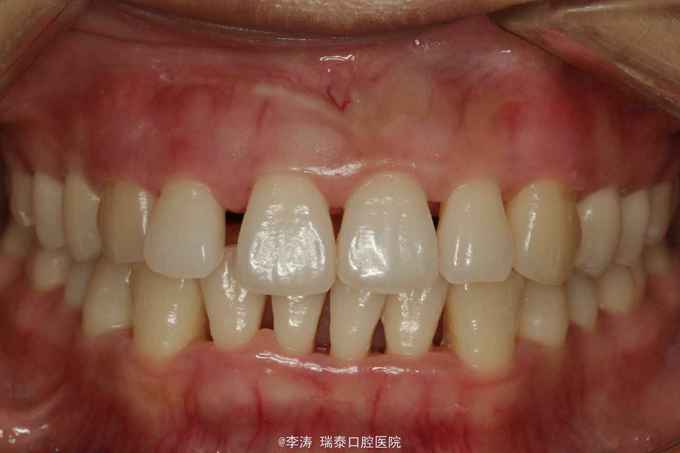

患者女24,主诉前牙缝隙就诊,自诉1年以前没有缝隙,现慢慢长大,刷牙出血

前牙间隙较大,全口牙龈红肿探诊出血,x线片,全口牙齿牙槽骨吸收至根中三分之一,牙周探诊示牙周袋深度均大于5mm

从症状和病史可诊断为急性牙周炎, 行全口洁治龈下刮治,牙周上盐酸米洛环素,一月后牙龈炎症消退,牙龈退缩使前牙可见明显间隙。